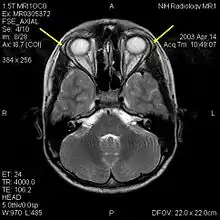

MRI of the brain of 12-year-old boy with triple-A syndrome showing hypoplastic lacrimal glands (yellow arrows)